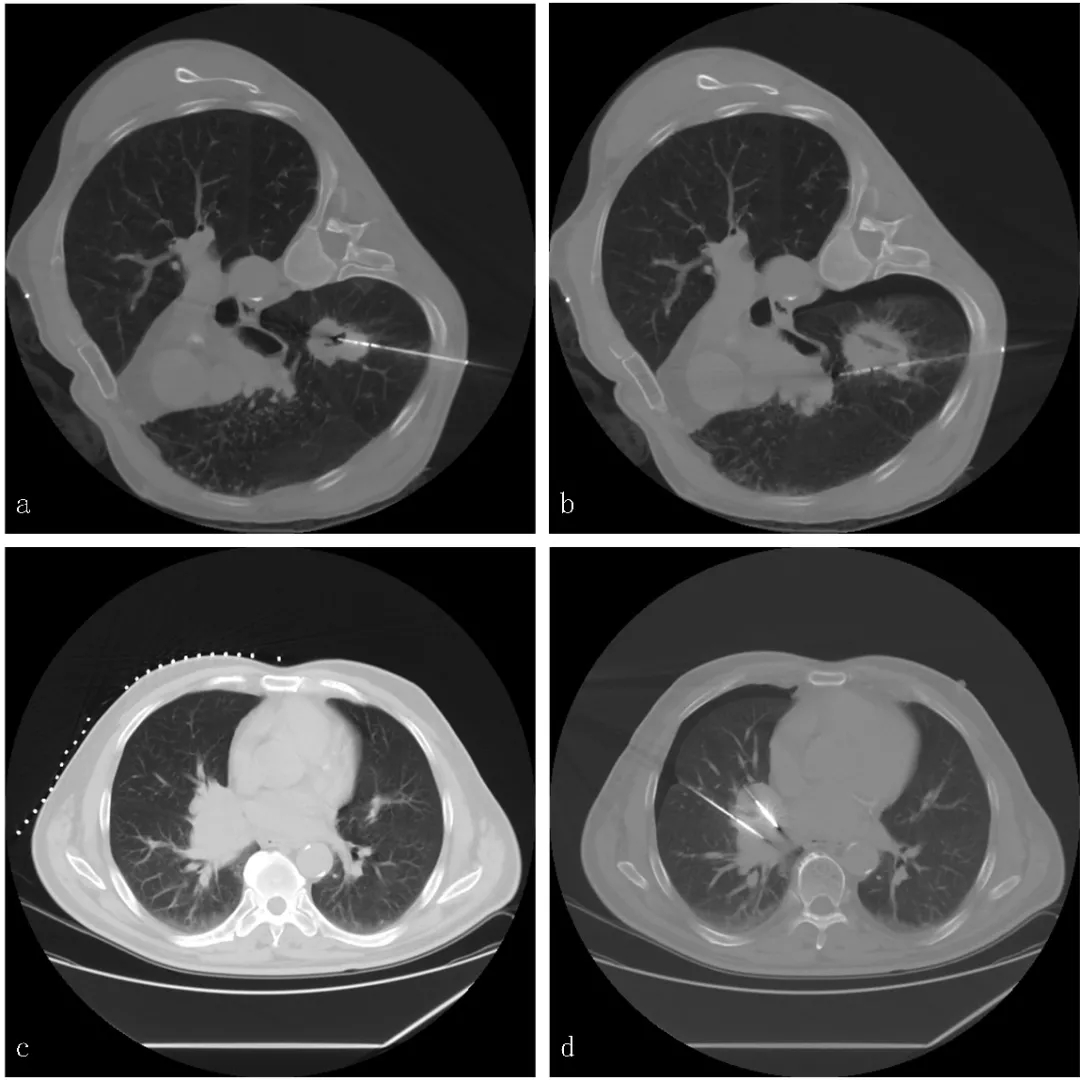

特殊类型及位于特殊部位的NSCLC是临床中常见的情况。文献报道空洞型NSCLC发生率约为2%-25%,侵犯叶间裂的NSCLC约为5.5%-17.1%。那么,热消融治疗是否可应用于这些患者呢?根据北京医院肿瘤微创治疗中心最新发表在JVIR杂志中的研究结果显示,MWA是空洞型NSCLC患者安全有效的治疗方式,且空洞型NSCLC患者接受MWA后的预后与非空洞型NSCLC患者相当。此外,该中心最新研究数据表明对于伴有叶间裂侵犯的NSCLC患者,尽管其在MWA术后有较高的气胸发生率,但其预后与不伴叶间裂侵犯的NSCLC患者相当,表明了热消融治疗的安全性及有效性。

我国范卫君教授团队研究表明,MWA可安全有效地应用于胸膜下肺癌患者的治疗,且肿瘤直径是影响疗效的主要因素。以上研究数据表明热消融是特殊类型或特殊部位的NSCLC患者安全有效的治疗方式,具体的技术操作方法仍需进一步探讨及共识。

图2. 特殊类型或特殊部位NSCLC的MWA治疗。a.空洞型NSCLC的MWA治疗,首先采取中心贯穿消融,有效消融空洞内壁的肿瘤细胞;b.然后采用逐步勾边消融,覆盖病灶边缘;c.侵犯叶间裂NSCLC患者;d.采用双MWA针,进行钳形消融治疗。